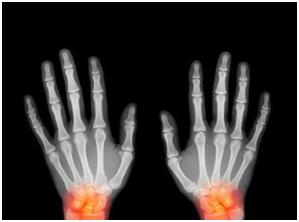

1 . 症状:起病缓慢,常有乏力、纳差、体重减轻及低热等全身症状。最常见以近端指间关节、掌指关节及腕关节为主的对称性、多关节、小关节肿痛,随着疾病发展逐渐出现关节活动受限,指关节呈梭形肿胀,晚期可畸形。晨僵的持续时间常与病情活动程度一致。

2 . 体征:对称性的关节肿胀、变形,活动受限,以四肢小关节多见,或可见皮下类风湿结节等[6]。

• RA:多表现为对称性小关节的红肿热痛,大关节也可受累,如指关节、腕关节、踝关节等;有晨僵,受累关节可出现畸形及功能障碍等。